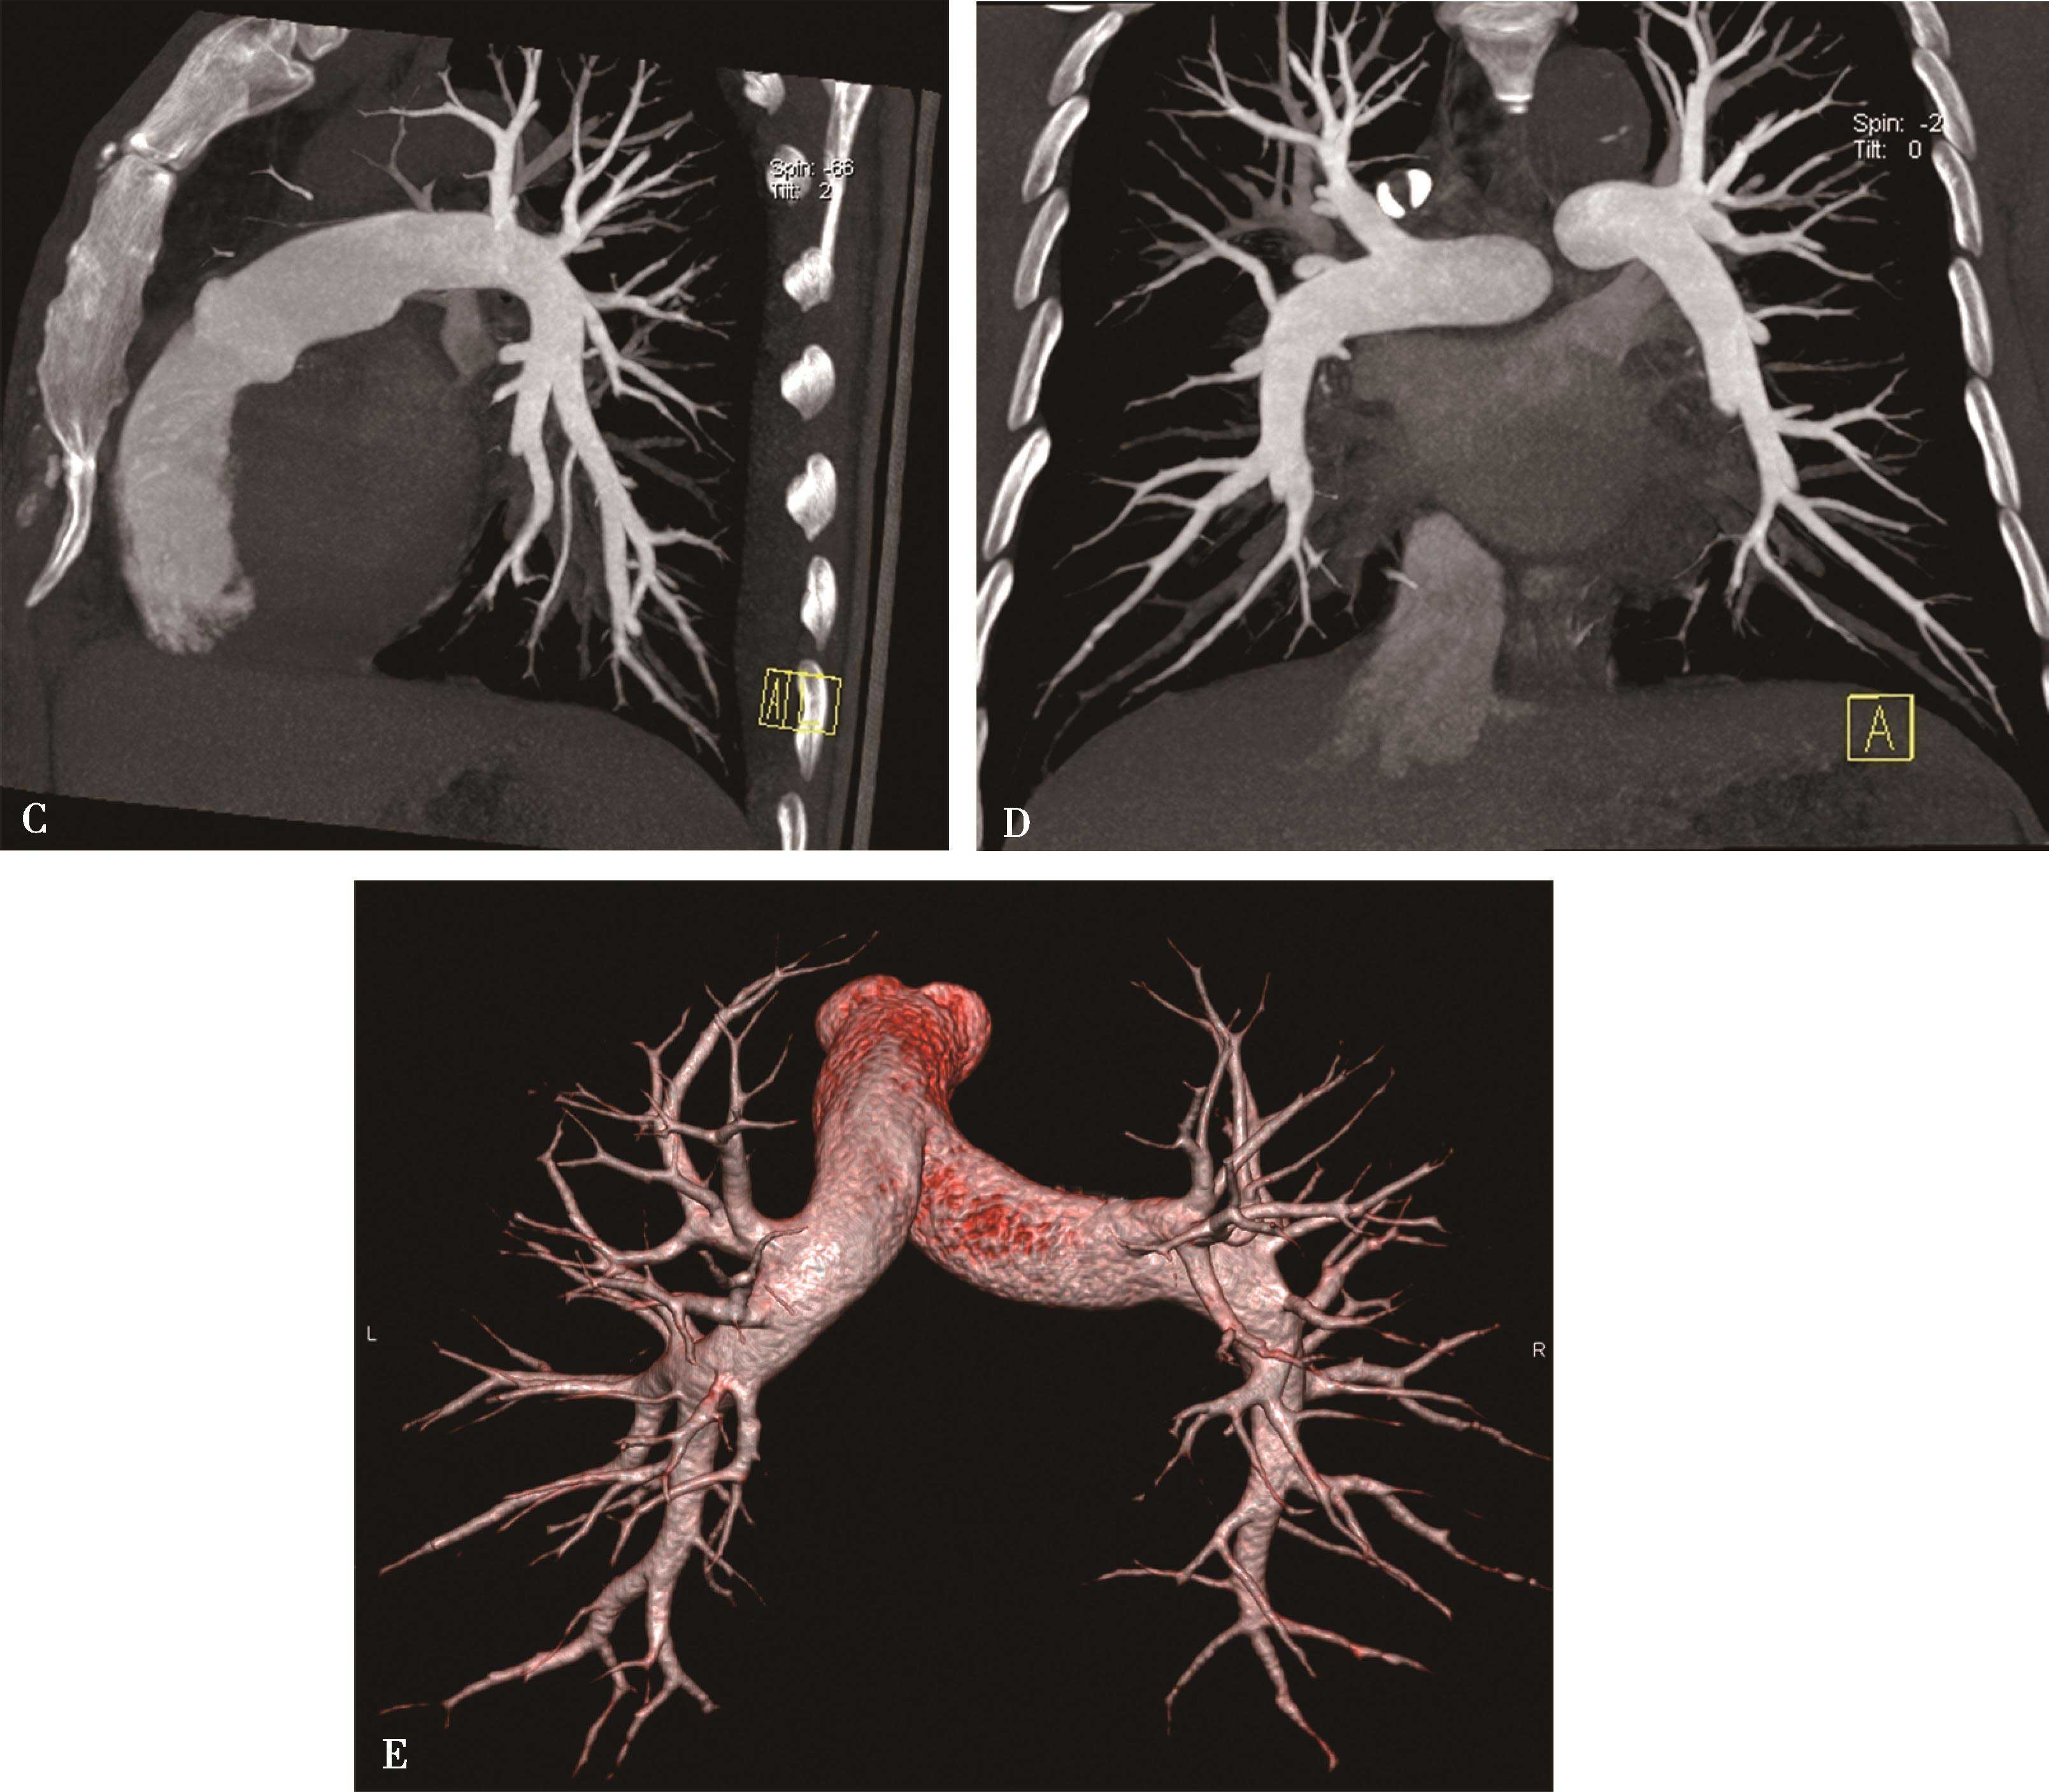

图8-4-12 慢性肺血栓栓塞性肺动脉高压(容积再现VR)

VR重建显示中心肺动脉明显扩张,远端分支明显纤细,迂曲、闭塞(↑)